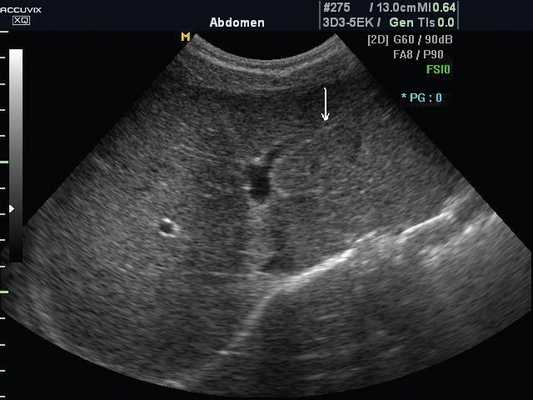

Женщина 50 лет, госпитализирована с болями в верхнем правом квадранте живота. Ультразвуковое исследование органов брюшной полости было проведено в день поступления (рис. 1а, б).

Рис. 1. УЗИ печени.

a) На эхограмме в правой доле печени видны два гиперэхогенных образования с четкими контурами (3,0x1,5 см, 2,5x1,5 см).

б) На эхограмме в левой доле печени видно большое гетерогенное образование (5.0x4.0 см), имеющее дольчатое строение.

Диагноз - множественная гемангиома печени